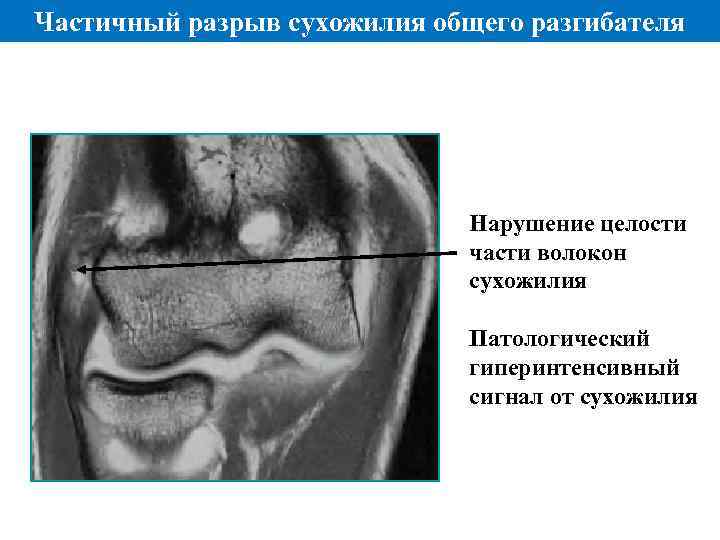

Частичный разрыв сухожилия общего разгибателя Нарушение целости части волокон сухожилия Патологический гиперинтенсивный сигнал от сухожилия

Частичный разрыв сухожилия общего разгибателя Нарушение целости части волокон сухожилия Патологический гиперинтенсивный сигнал от сухожилия